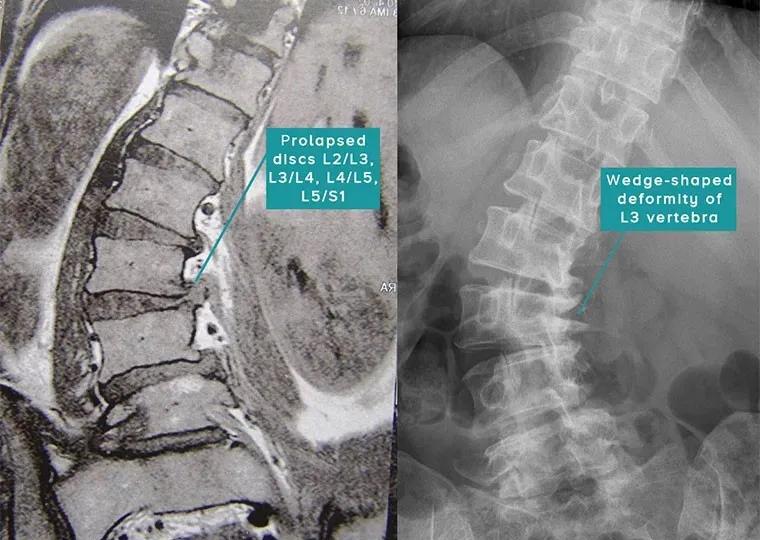

该患者年龄为40岁,胸部和腰椎40°Cobb S形脊柱侧弯,在其12岁时,就发现了脊柱侧弯。她的脊椎退化,有三个椎间盘突出,椎骨和椎间关节畸形。患者的下背部在坐下、站立、行走和躺下时翻身时都会感动疼痛。该患者在各种诊所接受了康复治疗,但没有任何改善。物理治疗师对患者进行了锻炼,这使她更加痛苦。患者的骨科专家建议对整个脊柱进行脊柱融合手术,该患者担心术后并发症,选择了非手术治疗,于是开始进行螺旋稳定治疗。

在进行了3个月的螺旋稳定训练之后,患者下背部疼痛明显减轻。经过6个月的螺旋稳定度训练后,疼痛完全消失,并开始像正常人一样工作。

T12-L4 38°Cobb-> 32°Cobb(提高6°)